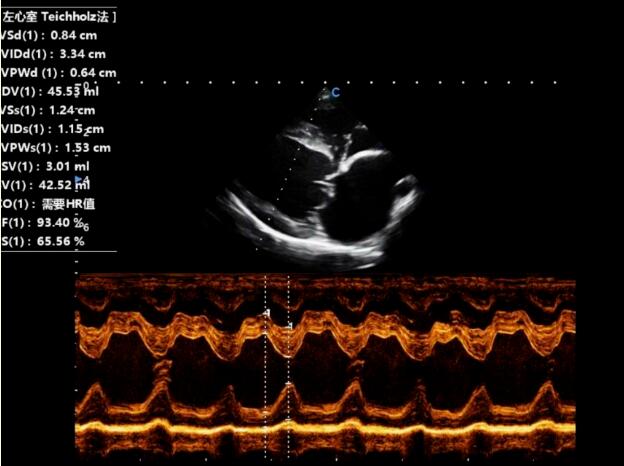

Then, the right parasternal short axis aortic section was taken to measure the ratio of the left atrium to the aorta, and the papillary muscle section was taken for M-mode echocardiography to measure the fractional shortening (FS).

The examination results of the dog's heart showed that, MMVD caused mitral regurgitation, and left ventricular systolic retrograde mottled blood flow.

Echocardiography is the most sensitive method for diagnosing MMVD. Through it, we can visually observe the imaging changes of the mitral valve structure and evaluate the intensity of reflux and the function of the heart. On echocardiography, MMVD are commonly observed with varying degrees of dilation of the left atrium and left ventricle, and the thickness of the heart wall mostly normal or slightly increased. During the contraction period, thickening of one or two leaflets , and tumor like lesions at the end of the leaflets can be observed, and in severe cases, the leaflets may also be shortened.